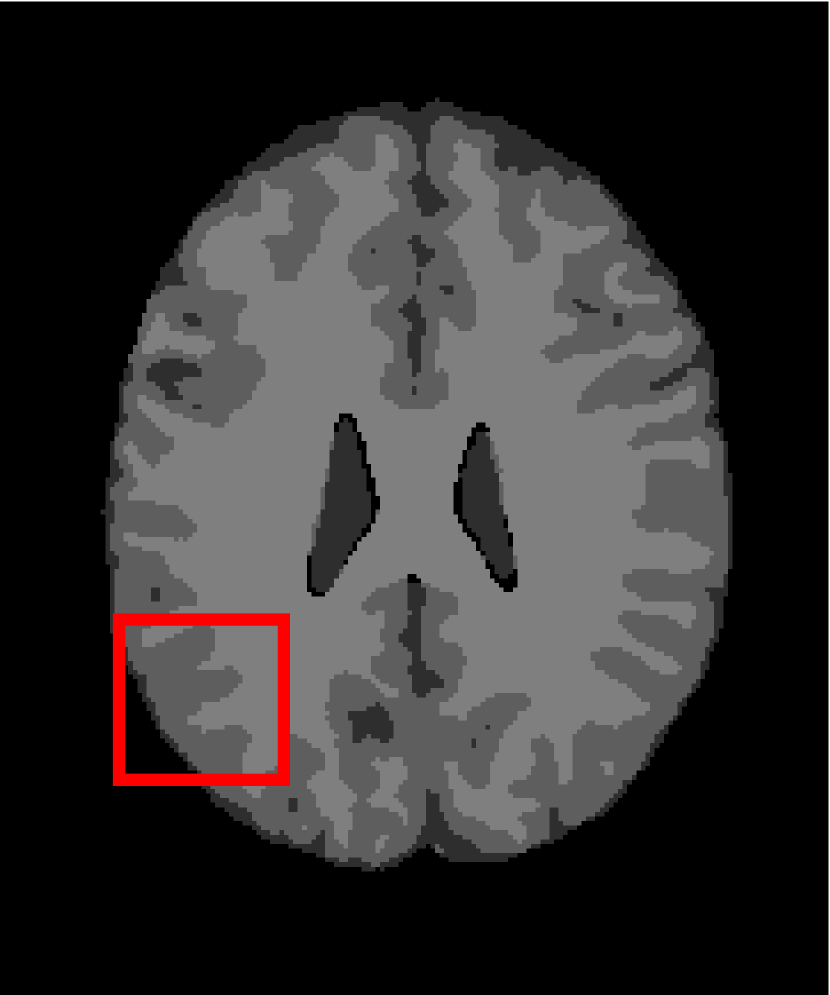

4.4.2 Results on Medical Images

Next, we representatively segment five medical images from BrianWeb. They are represented as five slices in the axial plane with a sequence of 70, 80, 90, 100 and 110, which are generated by T1 modality with slice thickness of 1mm resolution, 9% noise and 20% intensity non-uniformity. Here, we set c=4𝑐4c=4 for all cases. The comparison between WRFCM and its peers are shown in Fig. 9 and Table II. The best values are in bold.

Figure 9: Segmentation results on five medical images. The parameter: ϕ=5.35italic-ϕ5.35\phi=5.35. From top to bottom: noisy images, ground truth, and results of FCM_S1, FCM_S2, FLICM, KWFLICM, FRFCM, WFCM, DSFCM_N, and WRFCM.

By a view of the marked red square in Fig. 9, we find that FCM_S1, FCM_S2, FLICM, KWFLICM and DSFCM_N are vulnerable to noise and intensity non-uniformity. They give rise to the change of topological shapes to some extent. Unlike them, FRFCM and WFCM achieve sufficient noise removal. However, they produce overly smooth contours. Compared with its seven peers, WRFCM can not only suppress noise adequately but also acquire accurate contours. Moreover, it yields the visual result closer to ground truth than its peers. As Table II shows, WRFCM obtains optimal SA, SDS and MCC results for all five medical images. As a conclusion, it outperforms its peers visually and quantitatively.